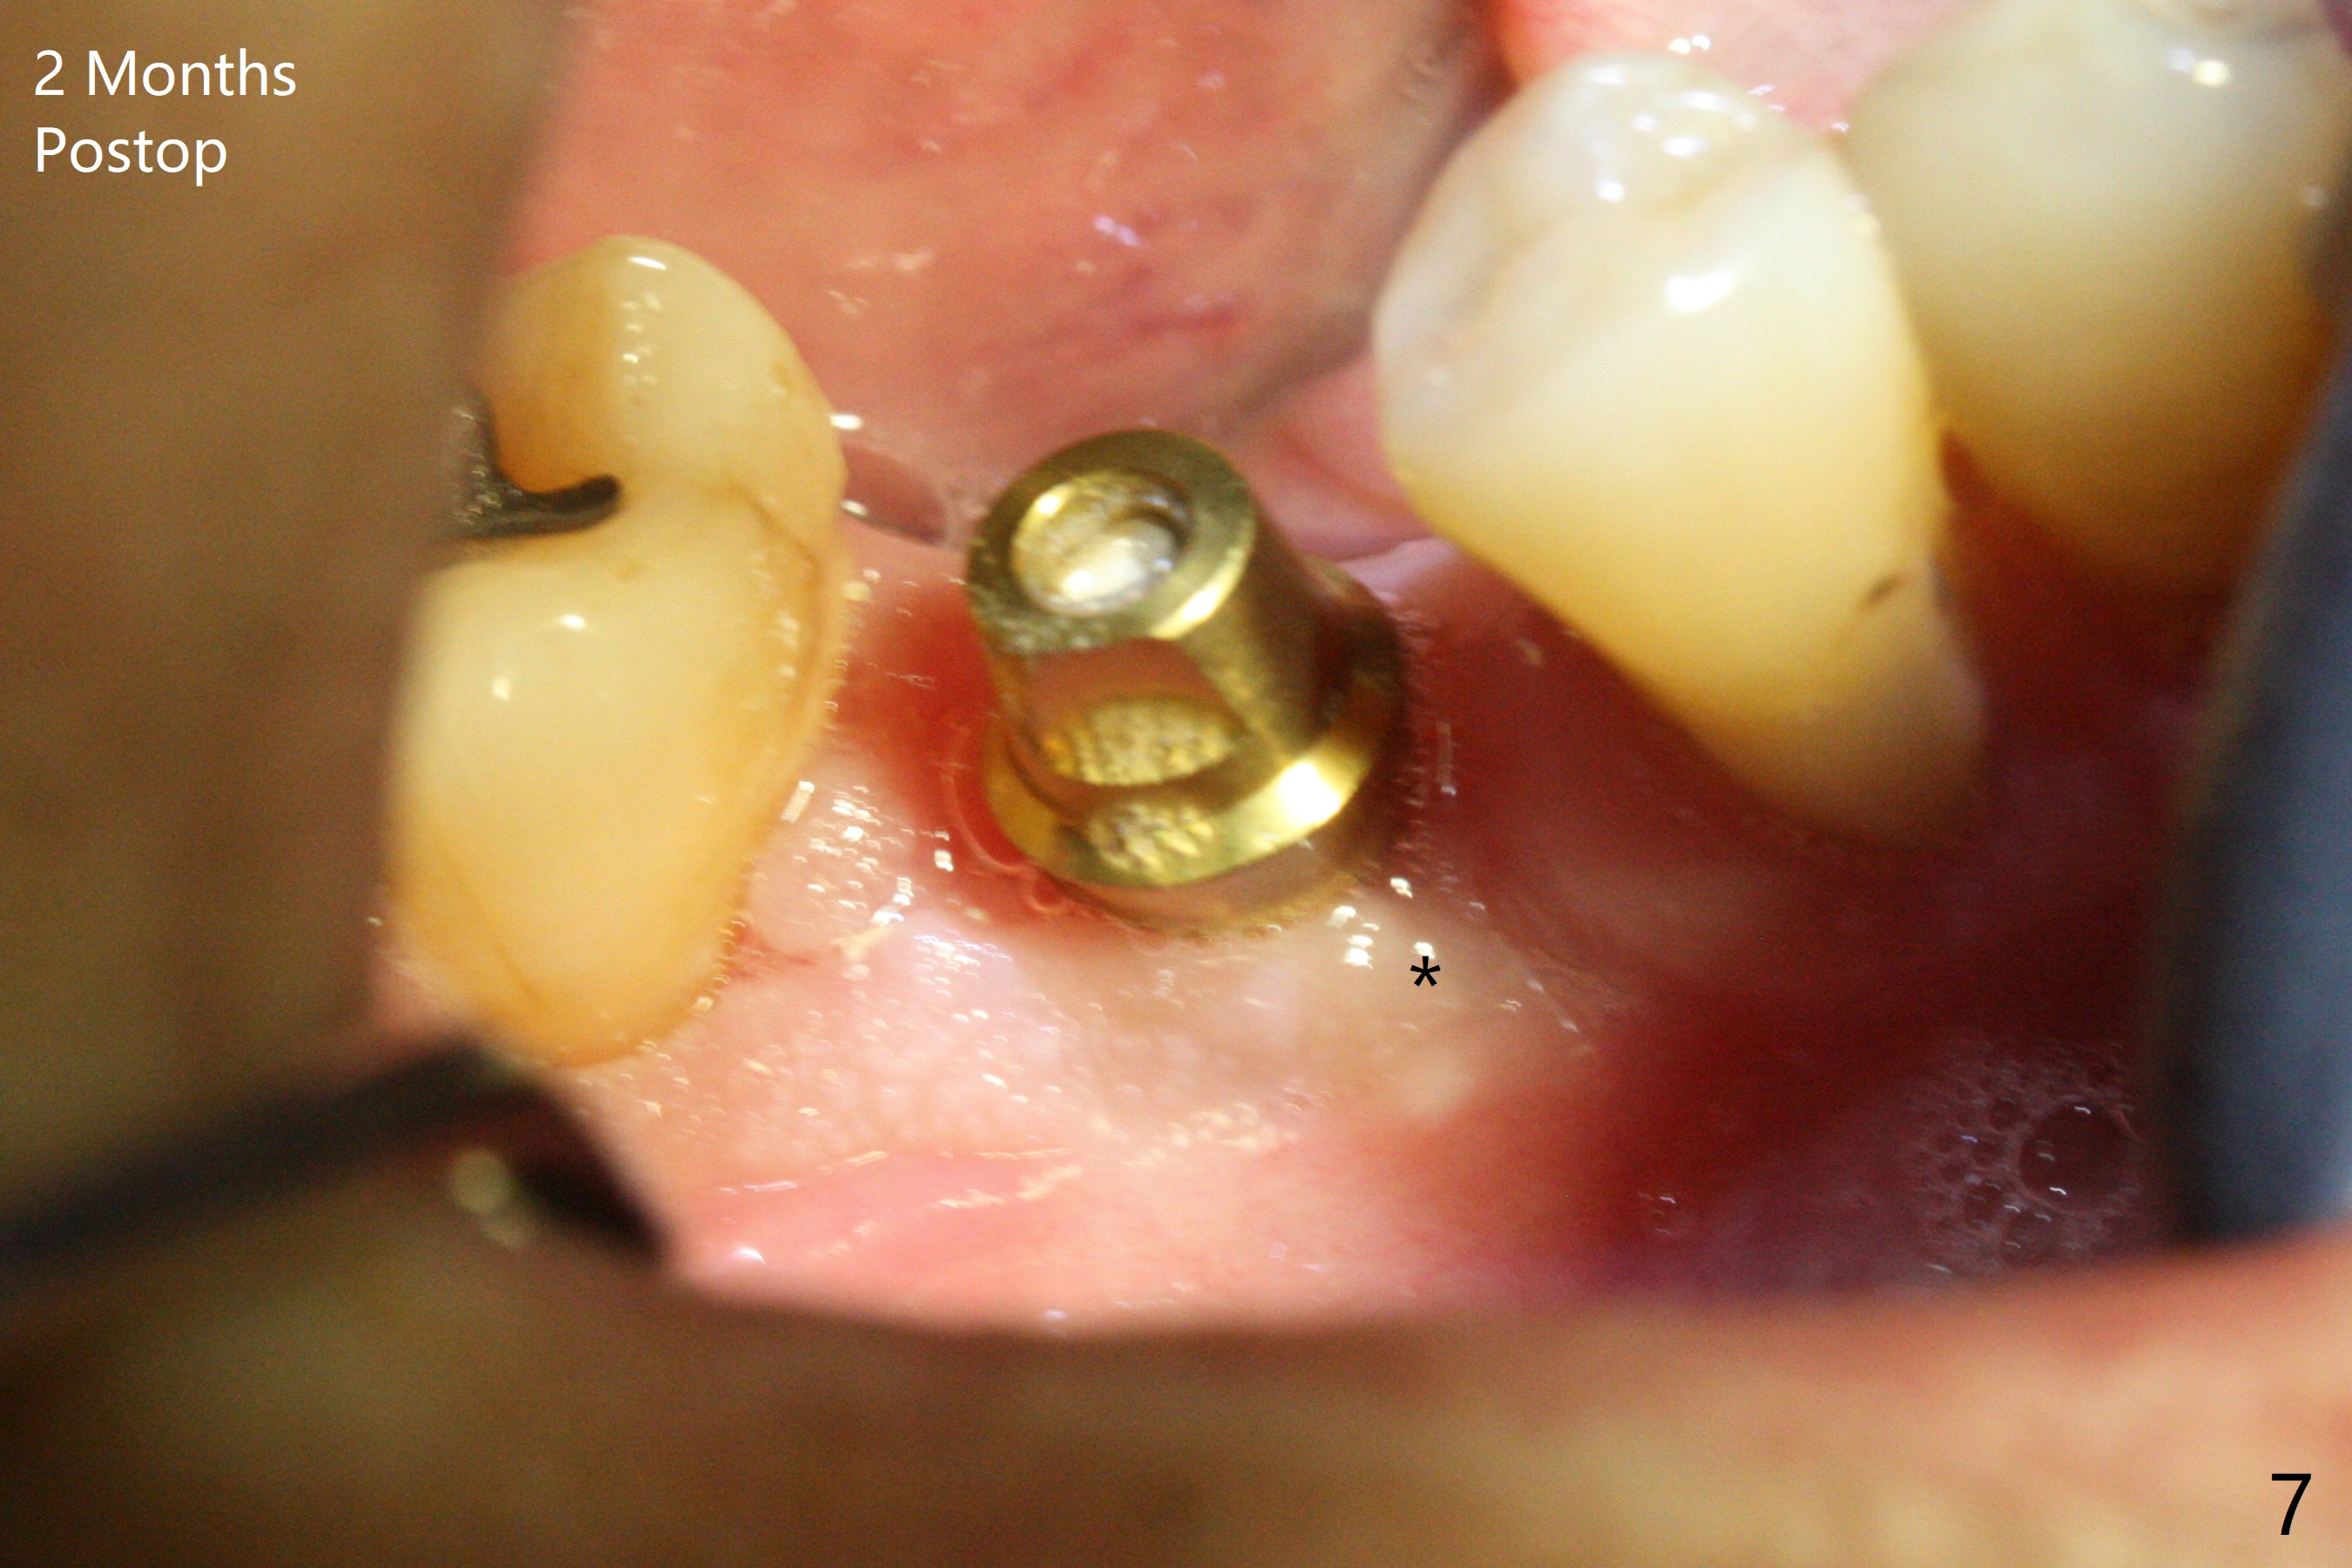

After extraction of the tooth #30, the mesiobuccal plate is found to be lost, corresponding to the fistula (Fig.1 <). Osteotomy is initiated in the flattened septum (lingual) for 13 mm (Fig.2). The patient feels pain when larger drills are being used. Marcaine has to be injected in an infiltration manner for pain control. When a 4.5x10 mm dummy implant is inserted with 55 Ncm, the end of the osteotomy (Fig.3 white line) is close to the Inferior Alveolar Canal (red dashed line). When a definitive implant (Fig.4: 4.5x11.5 mm) is placed with primary stability, there is an apical space (Fig.5 white double arrows). There is moderate postop pain. A shorter implant (10 mm) should be tried when the bone is dense. It will be associated with less pain. The fistula disappears 7 days postop (Fig.6). Although the patient appreciates that the pain is gone, there is atrophy mesiobuccally 2 months postop (Fig.7 *). The implant seems to be have been placed too buccally (Fig.8). With loss of the buccal plate, the implant should be placed away from it to prevent periimplantitis. The abutment is changed from 6.5x4(4) to 6.5x5.5 (3) mm with fabrication of a new provisional. The buccal margin is still supragingival 6 months postop and prep lower before impression. The mesial and distal sockets appear to have healed (Fig.9). When the crown is cemented, the mesiobuccal papilla is present (Fig.10 *), while the mesiolingual one is apparently absent (Fig.11 *). Using a temporary abutment and relining the provisional multiple times would increase the chance of rebuilding the missing papilla. The bone density around the implant increases 11 months post cementation (Fig.12). The dense (apparently cortical) bone seem to grow over the implant plateau 11 months post cementation (Fig.13 <).